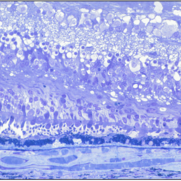

Best Vitelliform Macular Dystrophy

Best Vitelliform Macular Dystrophy

Dec 10 2020 by McGill University Health Centre

Postmortem eyes from 101-year-old female. Past clinical history includes a poor vision for many years due to macular degeneration. The last visual acuity test recorded 6/15 OD and 6/6 OS. IOP 14 and 18 torr OS. Histopathology: Disclosed and yellow 2x2mm macular lesion. Microscopic examination: elevated placoid macular lesion with overlying pigment granules. Electron microscopy examination: pigment granules with abundant lipofuscin and melanolysosomes, photoreceptor cells markedly attenuated (less degenerated at the periphery) Numerous calcified drusen throughout the retina particularly in the posterior pole. RPE lipofuscin content is elevated in Best’s dystrophy. The extractability of the PRE lipofuscin fluorophores is reduced (it is normal during senescence). The defect in Best’s dystrophy accelerates this age related change in lipofuscin.

Condition/keywords: Best vitelliform macular dystrophy (BVMD), fundus photograph